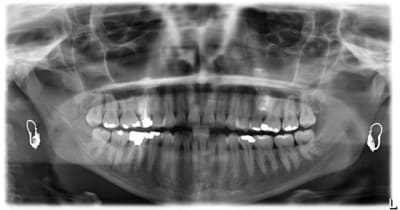

voici de la cas d'un jeune dame de 23 ans qui présente une full classe III subdivision Droite (associée à des compensations incisives de classe III), sur un terrain hyperdivergent. on note un encombrement inferieur d'environ 2 mm et une abrasion des bords triturants des incisives inf (Motif de la consultation)

on notera egalement de face une déviation de la pointe du menton vers la gauche.